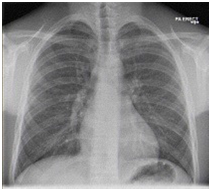

While still in the emergency department, he continued to have hemoptysis and developed palpable surgical emphysema at the root of the neck which raised suspicion of an ongoing air-leak from a TBI. A CT scan of the thorax was done and it showed a posterior tracheal tear 1.5cm above the carina as shown in Figure 2 and bilateral lung contusions, shown in Figure 3. His dyspnea and surgical emphysema continued to worsen, so he was intubated and immediately transferred to the nearest cardiothoracic centre.

Figure 2 CT Thorax transverse view showing posterior defect in the trachea.